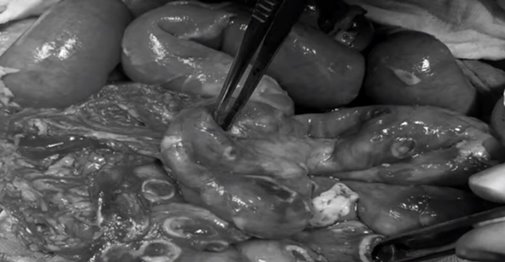

Old  Default Bác sĩ toát mồ hôi chứng kiến đường ruột bé trai bị thủng 50 lỗ do nhiễm giun sán

Suốt 6 tháng nay, bé trai đã được đưa đi khám ở nhiều nơi nhưng không tìm ra nguyên nhân, bé nhập viện trong tình trạng bụng chướng, sốt dai dẳng.

Hình ảnh đoạn ruột bị thủng 50 lỗ của cậu bé khi được phẫu thuật. Ngoài ra. bé còn bị nhiễm trùng, nhiễm độc.

Bác sĩ cho biết có thể cậu bé đã bị nhiễm ấu trùng giun sán khi chơi với chó mèo.